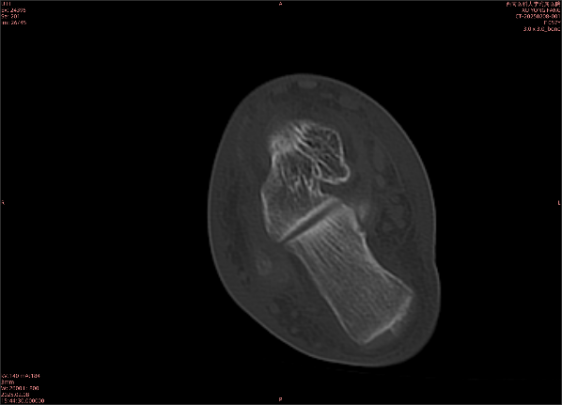

舉例圖像

圖1

圖2

專業(yè)解釋看不懂沒關(guān)系,大家看圖1和圖2就可以了,這是同一個(gè)患者跟骨的磁共振和CT圖像,圖1的紅色箭頭指示的黑線就是磁共振圖像顯示的骨折線,一目了然。而對(duì)比圖2的CT圖像上并未顯示異常。